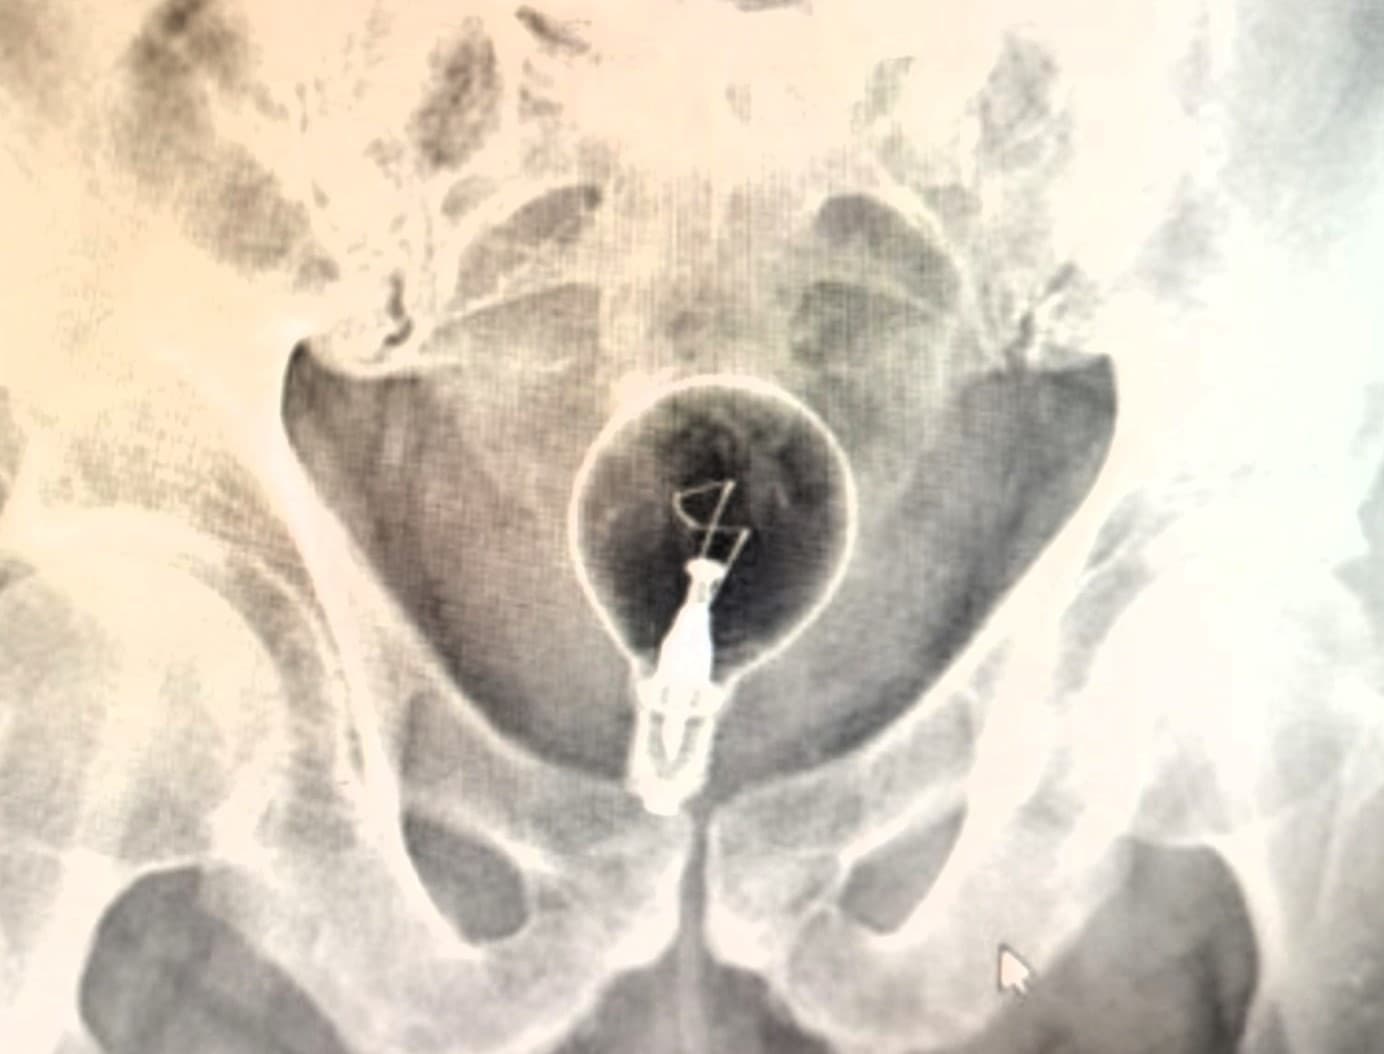

LECCE - Na pohotovosť v talianskom meste Lecce priviezli 85-ročného muža s nezvyčajným a nebezpečným problémom – v jeho konečníku uviazla žiarovka. Ako sa mu tam tento predmet dostal?

Starčekovi sa rýchlo zhoršil zdravotný stav po tom, čo ho jeho dcéra našla v silných bolestiach a s masívnym krvácaním. Privolaní záchranári následne objavili v jeho anorektálnej oblasti cudzí predmet a okamžite ho previezli do nemocnice Vito Fazzi.

Lekári tam zostali v šoku. U pacienta objavili klasickú žiarovku. Muž sa nepriznal, ako sa tam predmet dostal, no priznal, že sa ho snažil vytiahnuť skrutkovačom. Tým si spôsobil poranenia črevnej sliznice a zvýšil riziko vážnych komplikácií, vrátane infekcie, perforácie či sepsy. Incident sa odohral v utorok ráno 19. augusta, informuje na svojom webe needtoknow. Pod sedáciou absolvoval pacient endoskopický zákrok, pri ktorom lekári opatrne vytiahli žiarovku pomocou chirurgických klieští. Zariadenie zostalo, na prekvapenie všetkých, celé a nepoškodené.

Muž bol následne presunutý na oddelenie všeobecnej chirurgie na ďalšie pozorovanie, a to vzhľadom na jeho vysoký vek a drobné poranenia spôsobené neodborným zásahom. Hoci dôvody bizarného prípadu zostávajú nejasné, lekári nevylučujú, že mohlo ísť o nepodarený erotický experiment. Podľa miestnych médií sa však muž momentálne zotavuje a jeho stav je stabilizovaný.